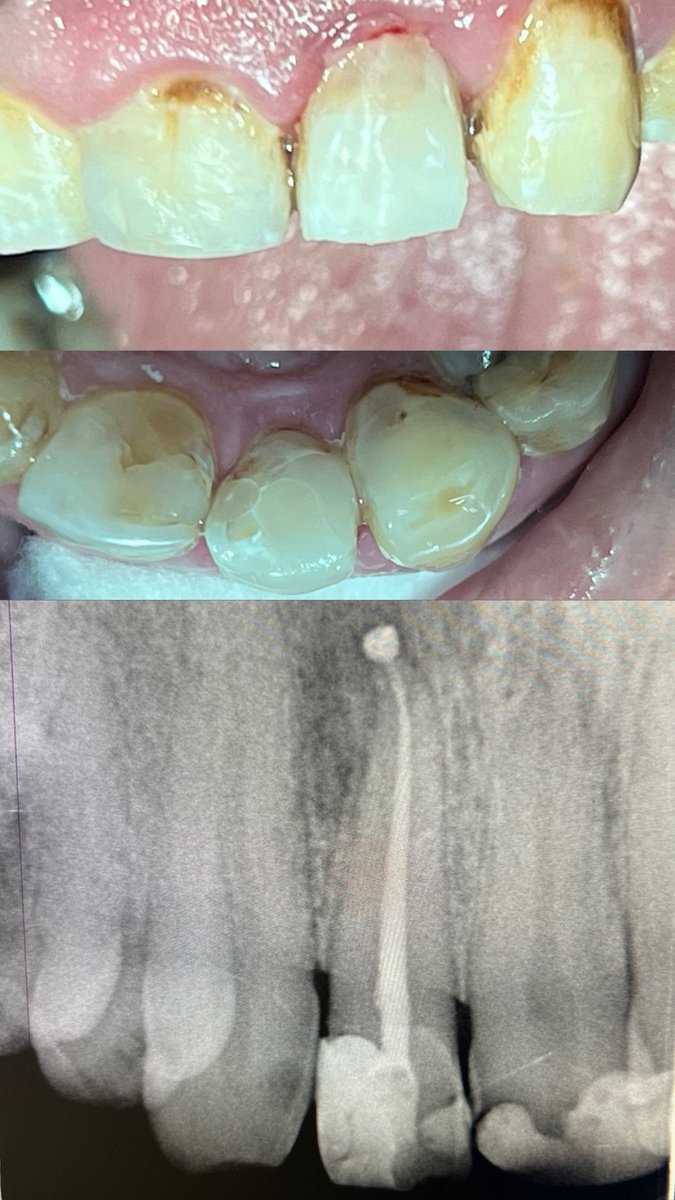

Today’s case:

Rct of #11 Dx : PI/AAA

• 1st visit: Open access, irrigation, abscess drainage, and dressing the canal with Ca(OH)₂.

• 2nd visit (after 30 days): Reopening the tooth, irrigation performed; the canal was completely dry and ready for obturation.

Patient is fine😁

English